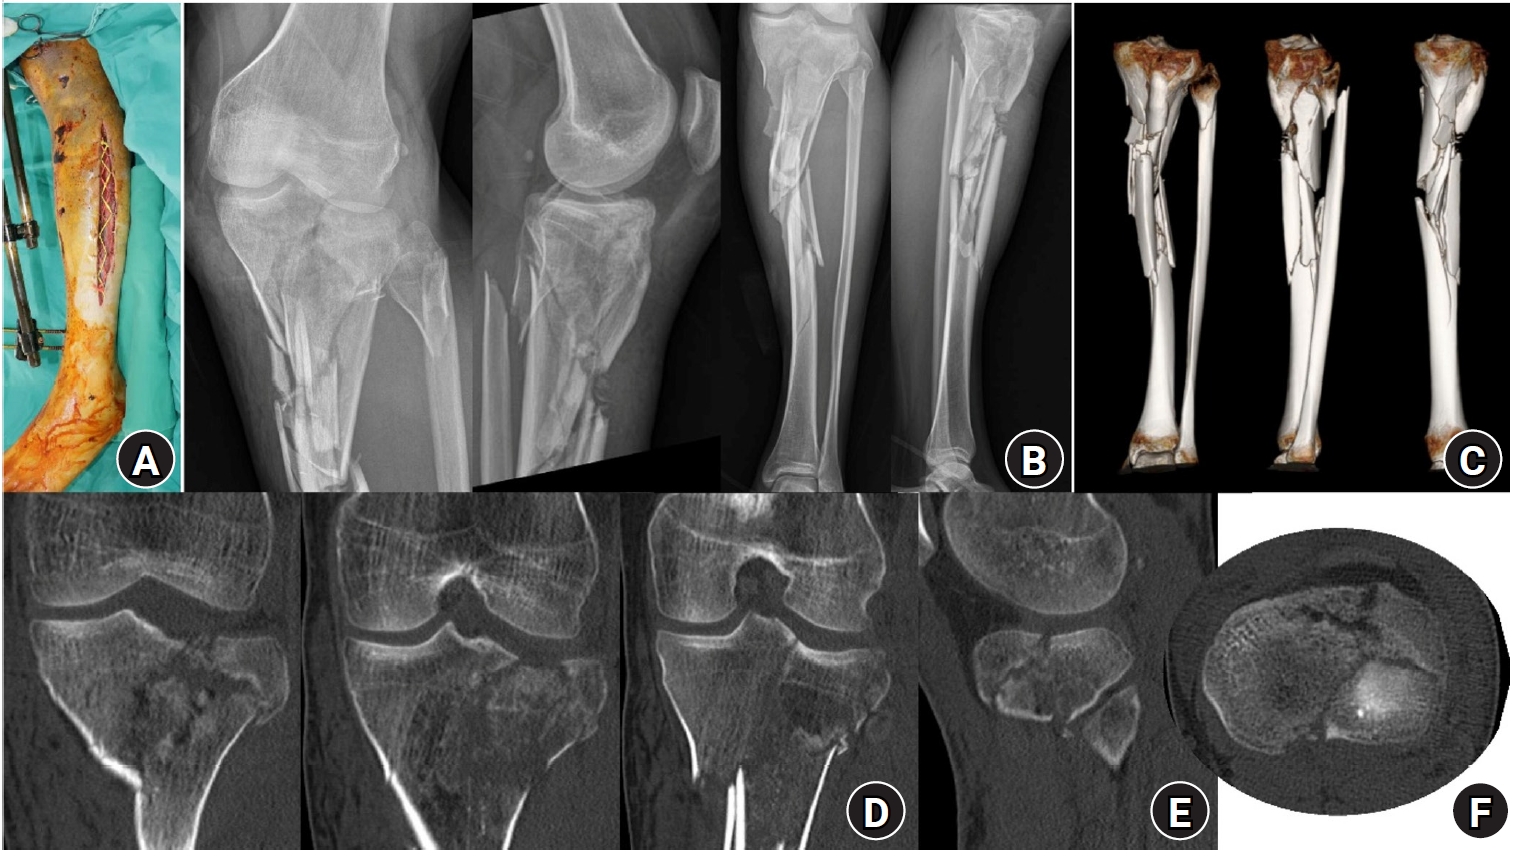

Fig. 5.

Preoperative photographs, plain radiographs, and computed tomography (CT) images. (A) Clinical photograph showing compartment syndrome of the lower leg with multiple necrotic skin contusions. (B) Preoperative plain radiograph. (C) Preoperative three-dimensional CT image. Preoperative coronal (D), sagittal (E), and axial. (F) CT images demonstrating depression and splitting of the lateral tibial plateau.

jmt-2025-00290f5.jpg